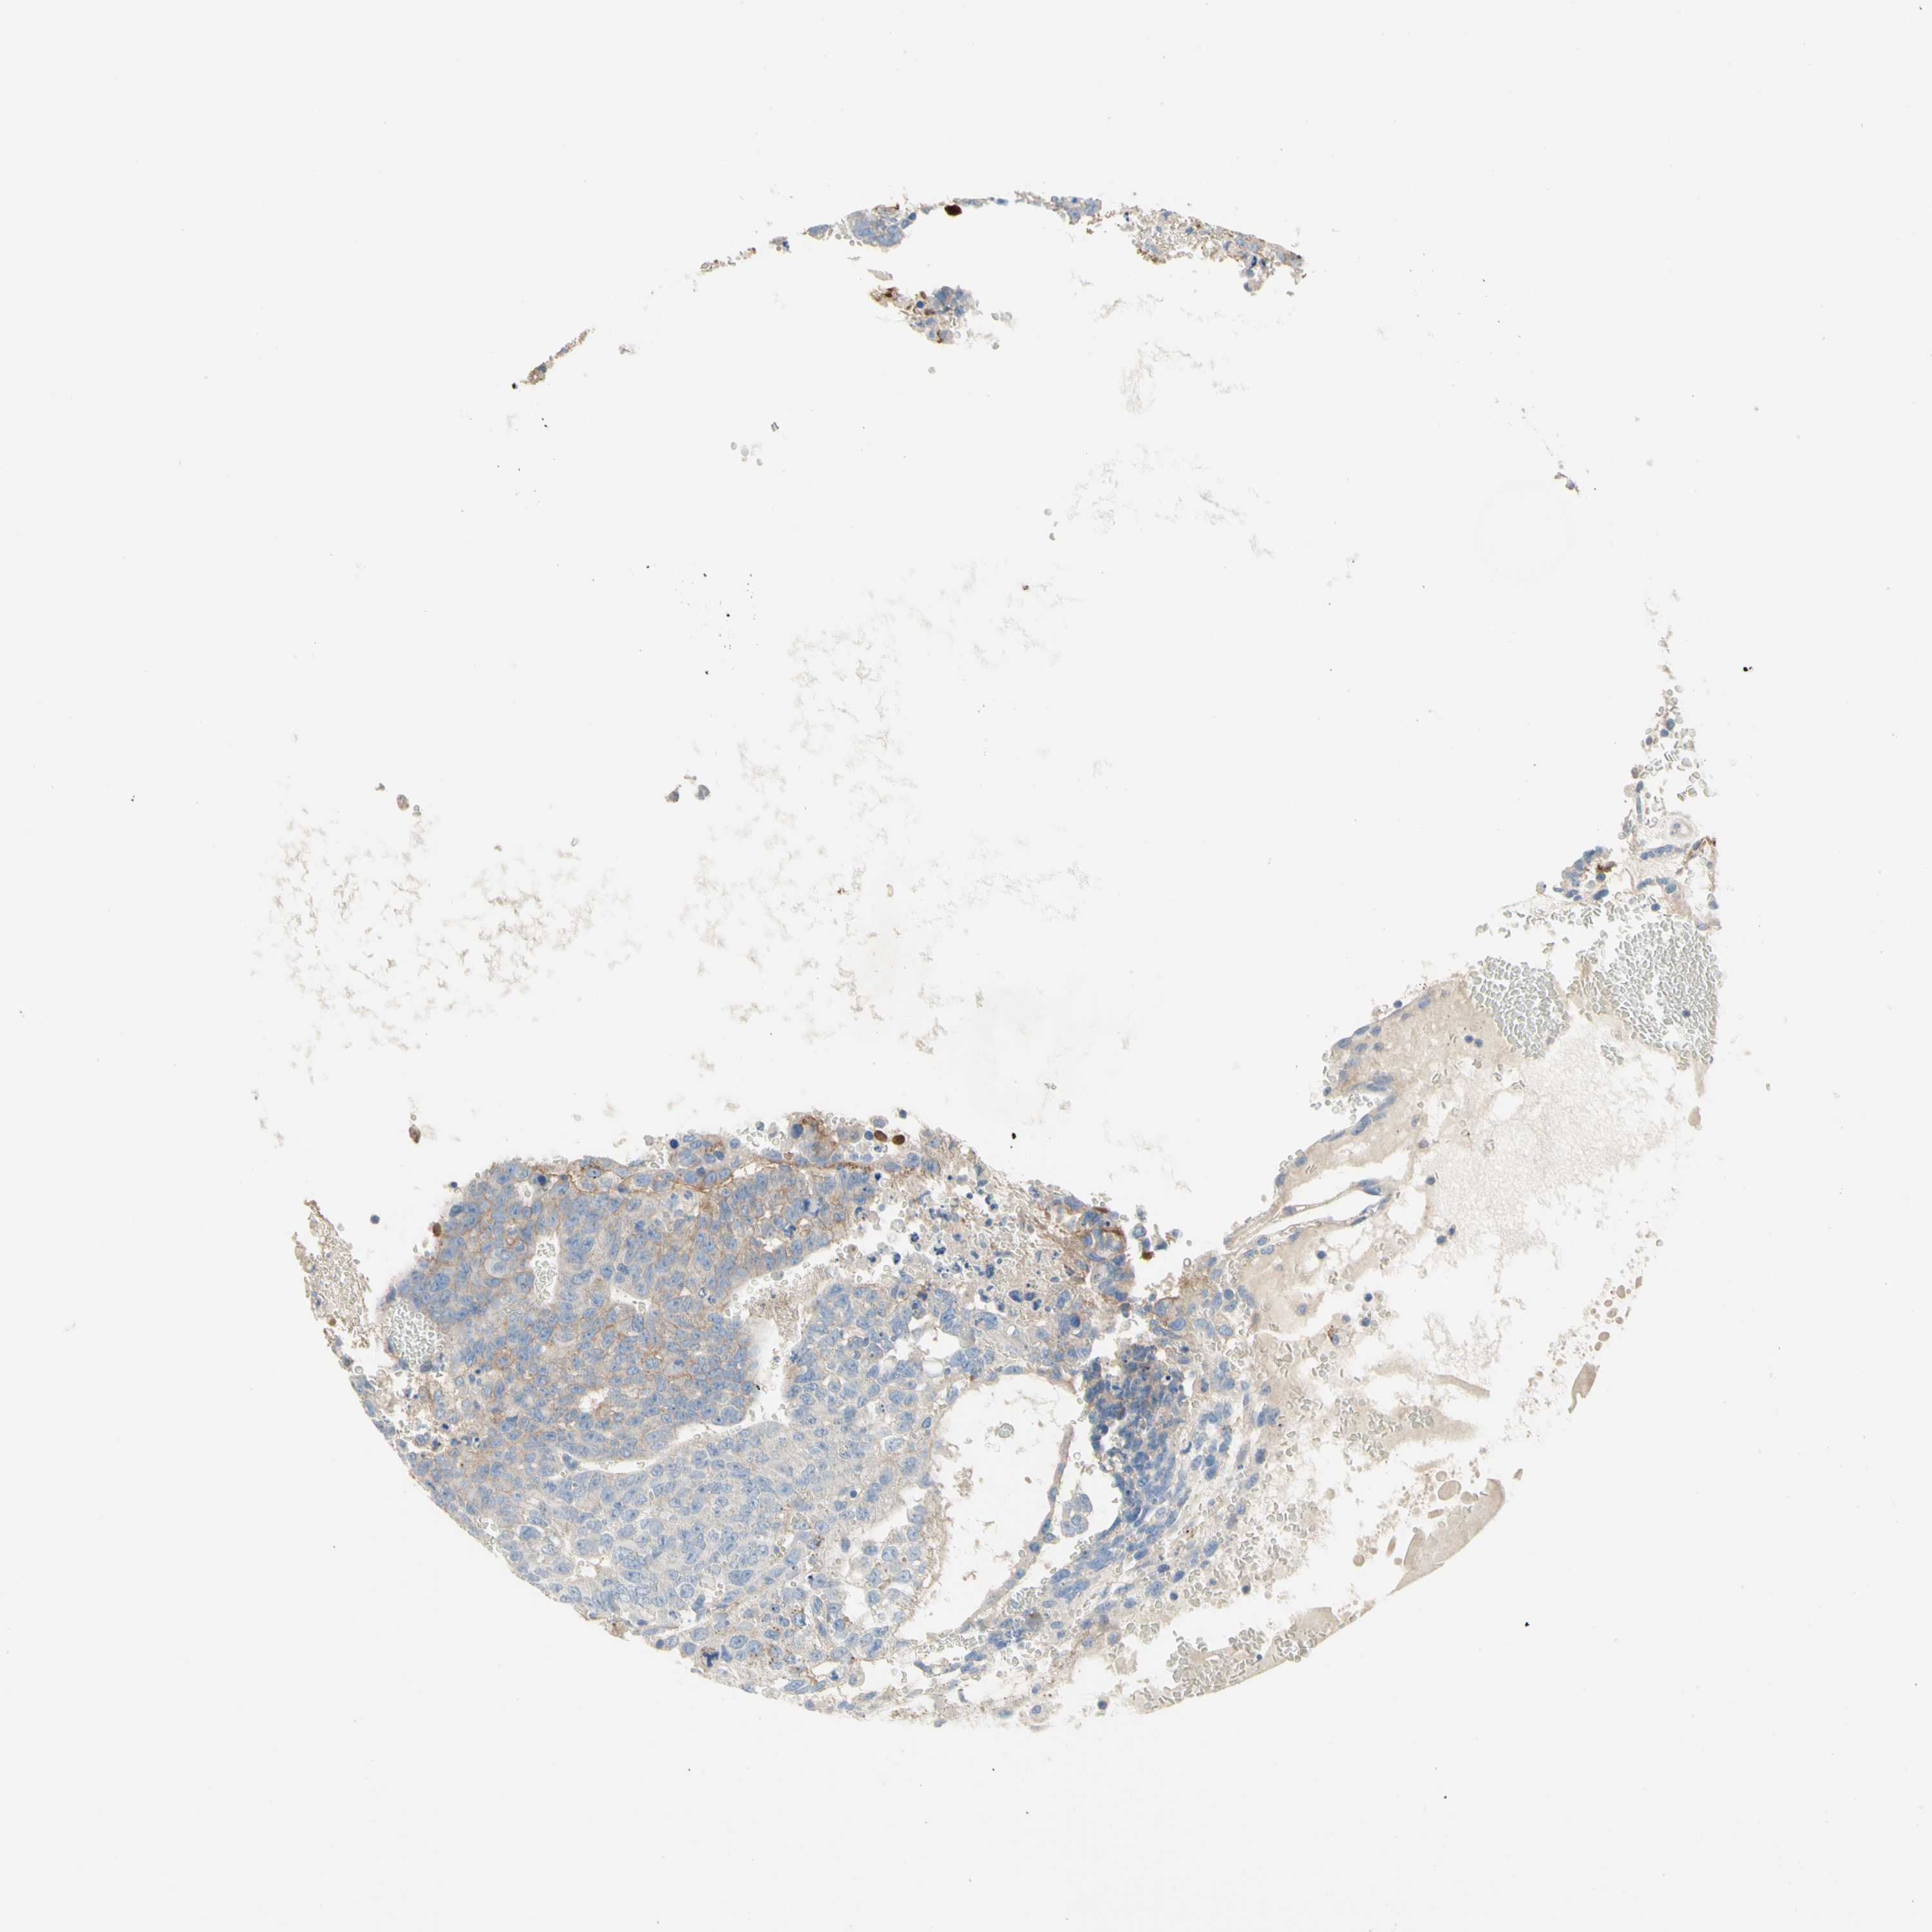

TESTIS CANCER - Protein expressioni

A mouse-over function shows sample information and annotation data. Click on an image to view it in a full screen mode. Samples can be filtered based on level of antibody staining by selecting one or several of the following categories: high, medium, low and not detected. The assay and annotation is described here.

Note that samples used for immunohistochemistry by the Human Protein Atlas do not correspond to samples in the TCGA dataset.

Antibody stainingi

Antibody staining in the annotated cell types in the current human tissue is reported as not detected, low, medium, or high, based on conventional immunohistochemistry profiling in selected tissues. This score is based on the combination of the staining intensity and fraction of stained cells.

Each image is clickable and will lead to virtual microscopy that enables deeper exploration of all samples and also displays staining intensity scores, fraction scores and subcellular localization as well as patient and tissue information for each sample.

Antibody HPA010775

Staining

High

Medium

Low

Not detected

Intensity

Strong

Moderate

Weak

Negative

Quantity

>75%

75%-25%

<25%

None

Location

Nuclear

Cytoplasmic/membranous

Cytoplasmic/membranous,nuclear

Carcinoma, Embryonal, NOS

Seminoma, NOS